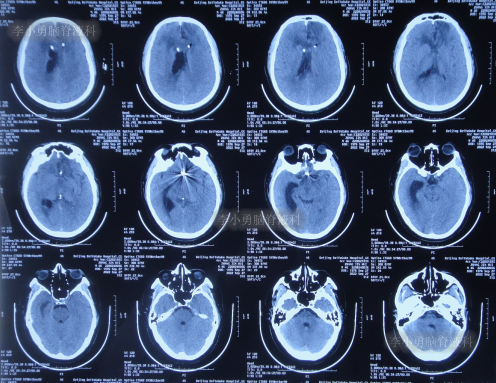

患者于2022年7月8日凌晨突发头痛,伴有胡言乱语,右下肢明显乏力,被家属送至附近的陕西省榆林市某医院,查头颅CT示脑出血(图-1),考虑脑动脉瘤破裂;当即给予了DSA检查发现前交通动脉瘤(图-2)。

图-1:2022年7月8日头颅CT